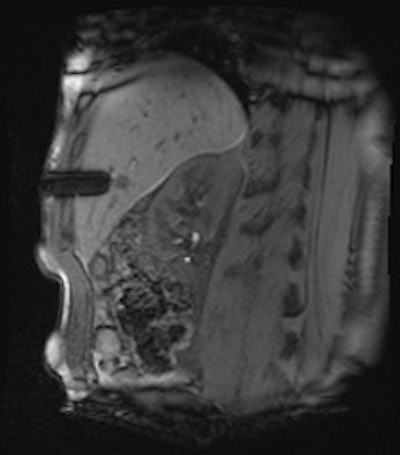

A 50-year-old man with history of pancreatic carcinoma underwent a CT-guided biopsy (above), which was nonconclusive (pathology result: normal liver tissue). Three weeks later, an MR-guided biopsy (below) was performed, and the biopsy revealed a cavernous hemangioma. Images courtesy of Dr. Rüdiger Hoffmann.